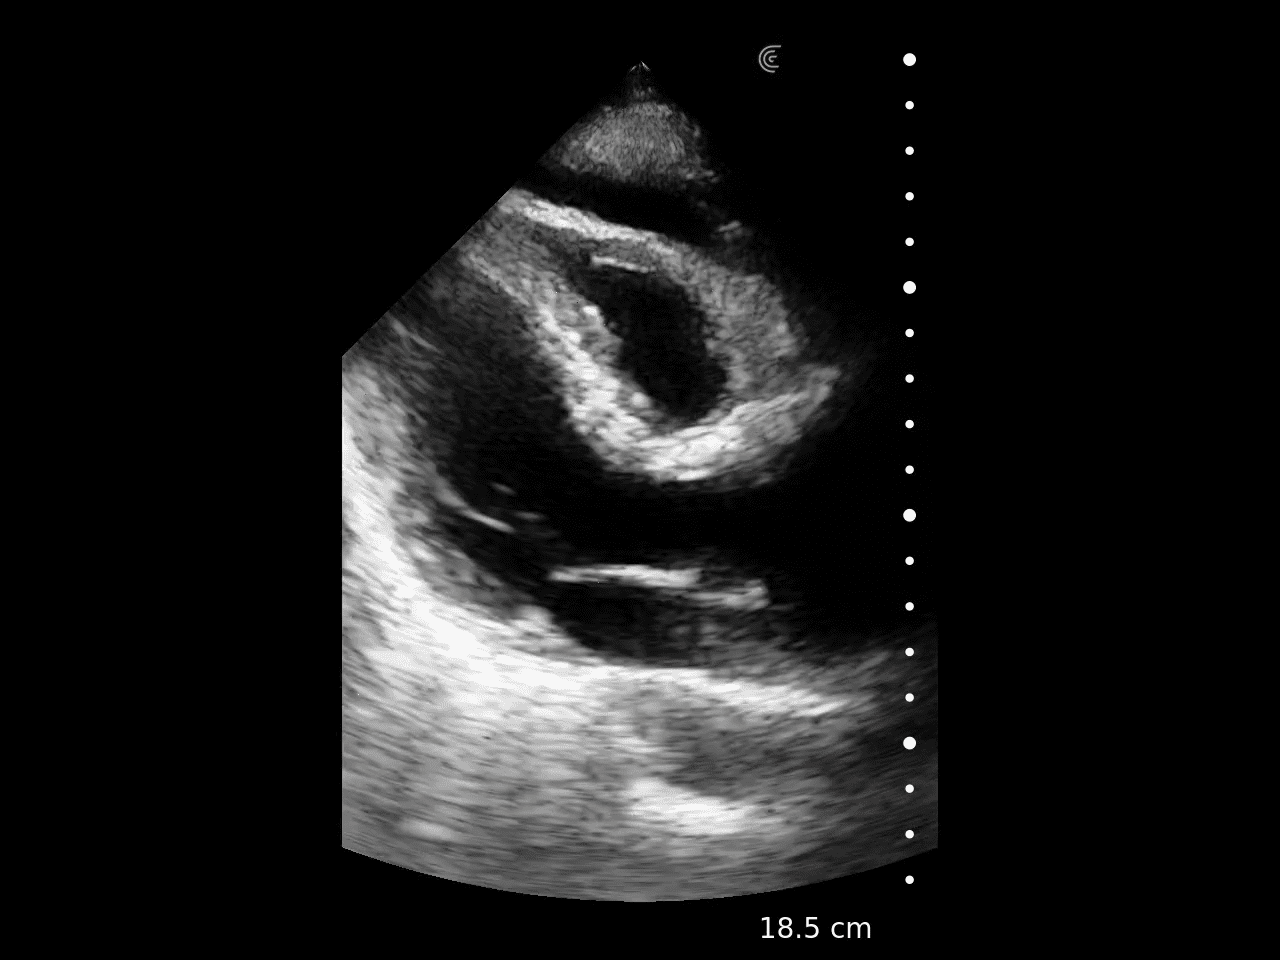

Desempenhe exames cardíacos à beira-leito com imagens de alta resolução em um transdutor sem fio.

Pequeno e com imagens profundas, o Clarius PA HD3 oferece imagens do tórax e abdômen de altíssima definição em até 40cm.

É a principal escolha para médicos que procuram imagens cardíacas diferenciadas em um transdutor ultraportátil perfeito para exames FAST, imagens superficiais e transcranianas.

Com 192 elementos e tecnologia de 8 feixes, o Clarius entrega alta performance nos ultra portáteis com qualidade de imagem e recursos equiparáveis aos equipamentos high end convencionais.